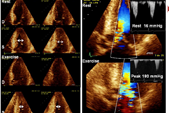

Hypertrophic cardiomyopathy (HCM) is a relatively frequent genetic disease that affects 1/500 human beings. Main problems with this disease are the development of symptoms in 10-20% of affected individuals, and the increased risk of sudden cardiac death (SCD) in a subset of patients with the disease. It is important to clarify the cause of symptoms and to assess the risk of sudden death in HCM because we do have therapies to relief these problems.